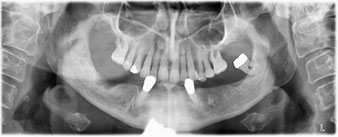

La patiente âgée de 64 ans présente une denture résiduelle des dents 38, 33 et 43 et une prothèse amovible mandibulaire stabilisée par crochets (Fig. 1 et 2).

Un CT Scan à faisceaux coniques tridimensionnel (CBCT, Planmeca) a été réalisé au préalable afin de réduire les risques. Il a révélé une qualité et une quantité d'os disponible suffisante pour l'intervention chirurgicale et la restauration immédiate par la méthode All-on-four. En suivant le protocole de ce concept, les implants sont insérés au niveau de 35, 32, 42 et 45 en inclinant les implants distaux jusqu'à 45°, le profil d'émergence se déplace ainsi vers l'arrière et produit un polygone de stabilisation plus large (Fig. 3).